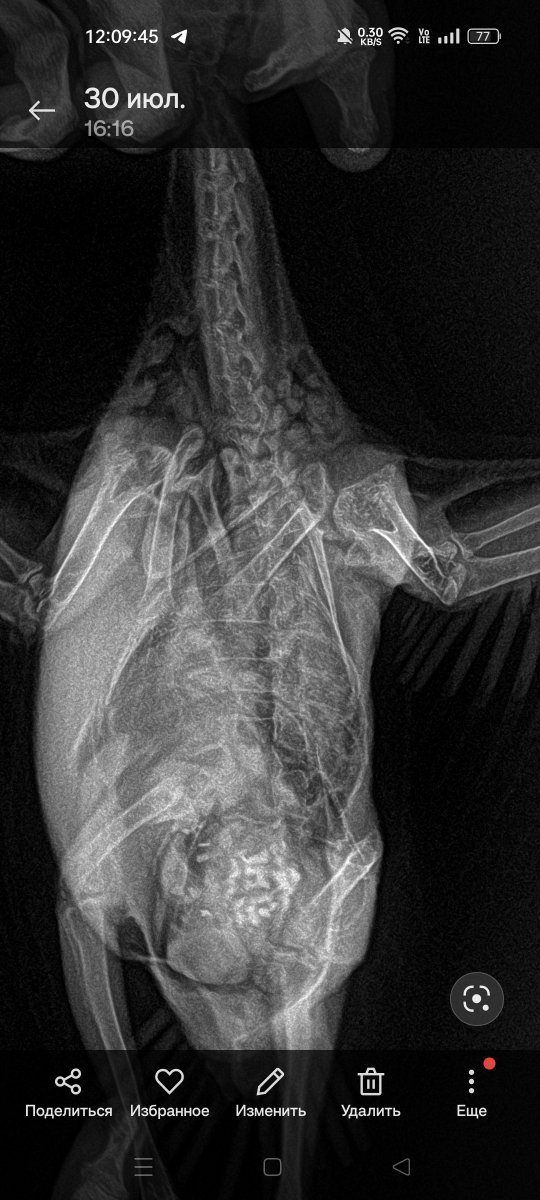

Здравствуйте! В июне 7 числа на проезжей части в ночи нашла голубя, ему было 1:5 месяца, глаза в гное + ушибы , отсутствие хвоста и половины перьев , волочил ножку. Пролечились от Мико ( Нистатин+ Распивет+ геповет+ Бифидумбактерин) , сделали рентген в двух проекциях, сказали что он плохой и надо переделывать, не читаемый, но по нему видно что у птицы пневмония? И камни в ноге( гастролит) . Три анализа микло+ сальмонеллёз+ орнитоз отрицательный. Ситуация следующая: голубь подрос, вес набрал с 174 до 300 и после резко стал худеть,  спустя месяц как закончили лечение вернулось чихание, поджимает лапку( выглядит она не здоровой) стал хохолится, отказ от еды, выбирает просо( и то только цветное должно быть , красное/ жёлтое/ чёрное) кормлю третий день кашей Хайнц, чихать после приёма еды стал меньше, ноооо, настораживает резкое похудение , вялость в плане что мало играется с игрушками , стал больше отдыхать, стоит на одной ножке, и горло по ощущениям внутри опухло? Как мышцы трогаю , какашки не булочкой, хохолится, в комнате 23. Пожалуйста помогите Чиполлино: в первую очередь понять для меня  что есть нормально в период линьки, могут ли это быть паразиты ( не глистогонила , ибо был слабый и куча АБ которое менялось три раза ) и вернулось ли Мико? Что делать с пальцем .., Прошу прощения за не совсем адекватные вопросы , но , у меня уже была создана здесь тема о голубе ( год назад, Стёпа) он задохнулся и умер , на как понимаю теперь это вертячка + зерно в трахею попало, очень боюсь повторить эту трагедию. Чиполлинино чистит перья, кушает листики овса , курлыкает. Прикрепляю фото каким был и какой на данный момент+ фото пальца левой лапки и общий вид птицы . Огромное спасибо всем кто откликнется на эту тему и сможет помочь успокоить меня и направить верно на анализы по инфекции ЖКТ, вдруг грибы или паразиты внутри , тем самым спасти жизнь Чиполлино. Если такова угроза присутствует.